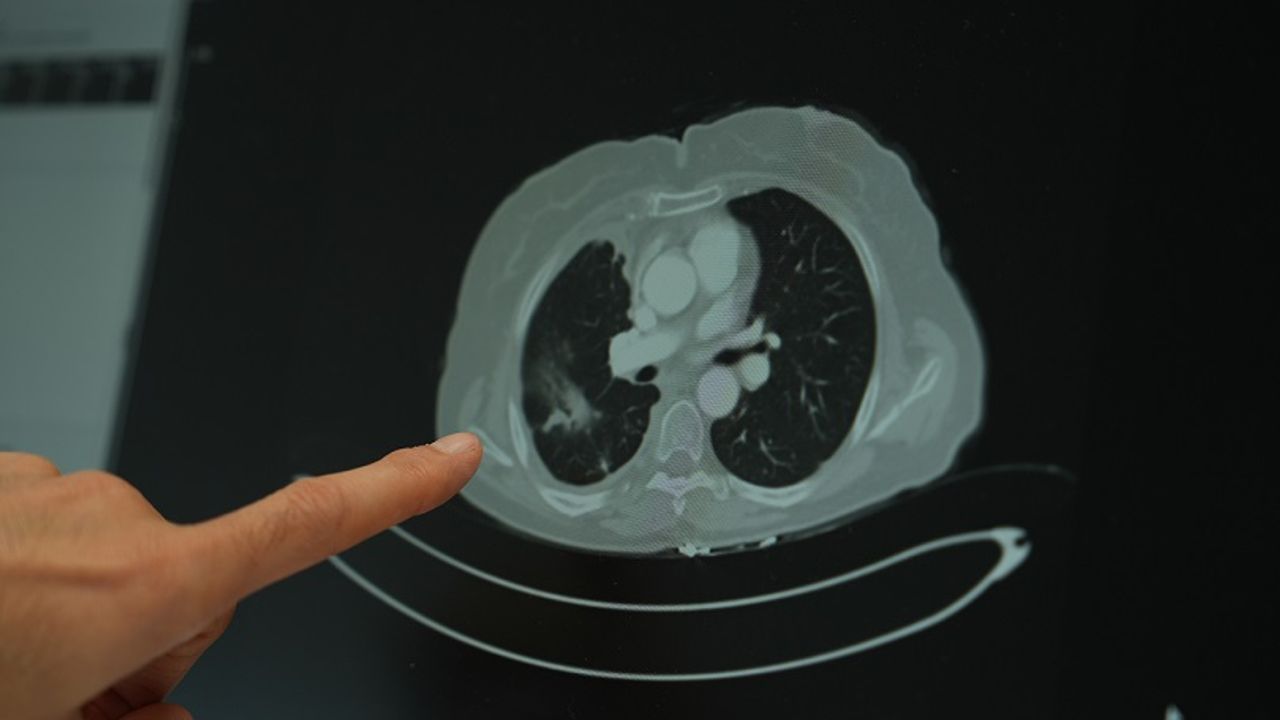

Ailesinde kanser öyküsü bulunan gençlerin çok daha dikkatli olması gerektiğini vurgulayan Doç. Dr. Şimşek, “Ailede kanser varsa, tarama yaşları çok daha genç yaşlara çekilebiliyor. Bazı durumlarda 18-20 yaşlarından itibaren düzenli kontrollerin yapılması hayati önem taşıyor” diye konuştu. Sigara kullanımının akciğer kanseri üzerindeki etkisini değerlendiren Doç. Dr. Şimşek, uzun süre sigara kullanan kişilerde düşük doz radyasyonla yapılan tomografi taramalarının önerildiğini belirterek “Sigara içen bireylerde akciğer kanseri riski yüksek. Bu nedenle düşük doz radyasyonlu taramalar, erken tanı açısından önemli” ifadelerini kullandı.